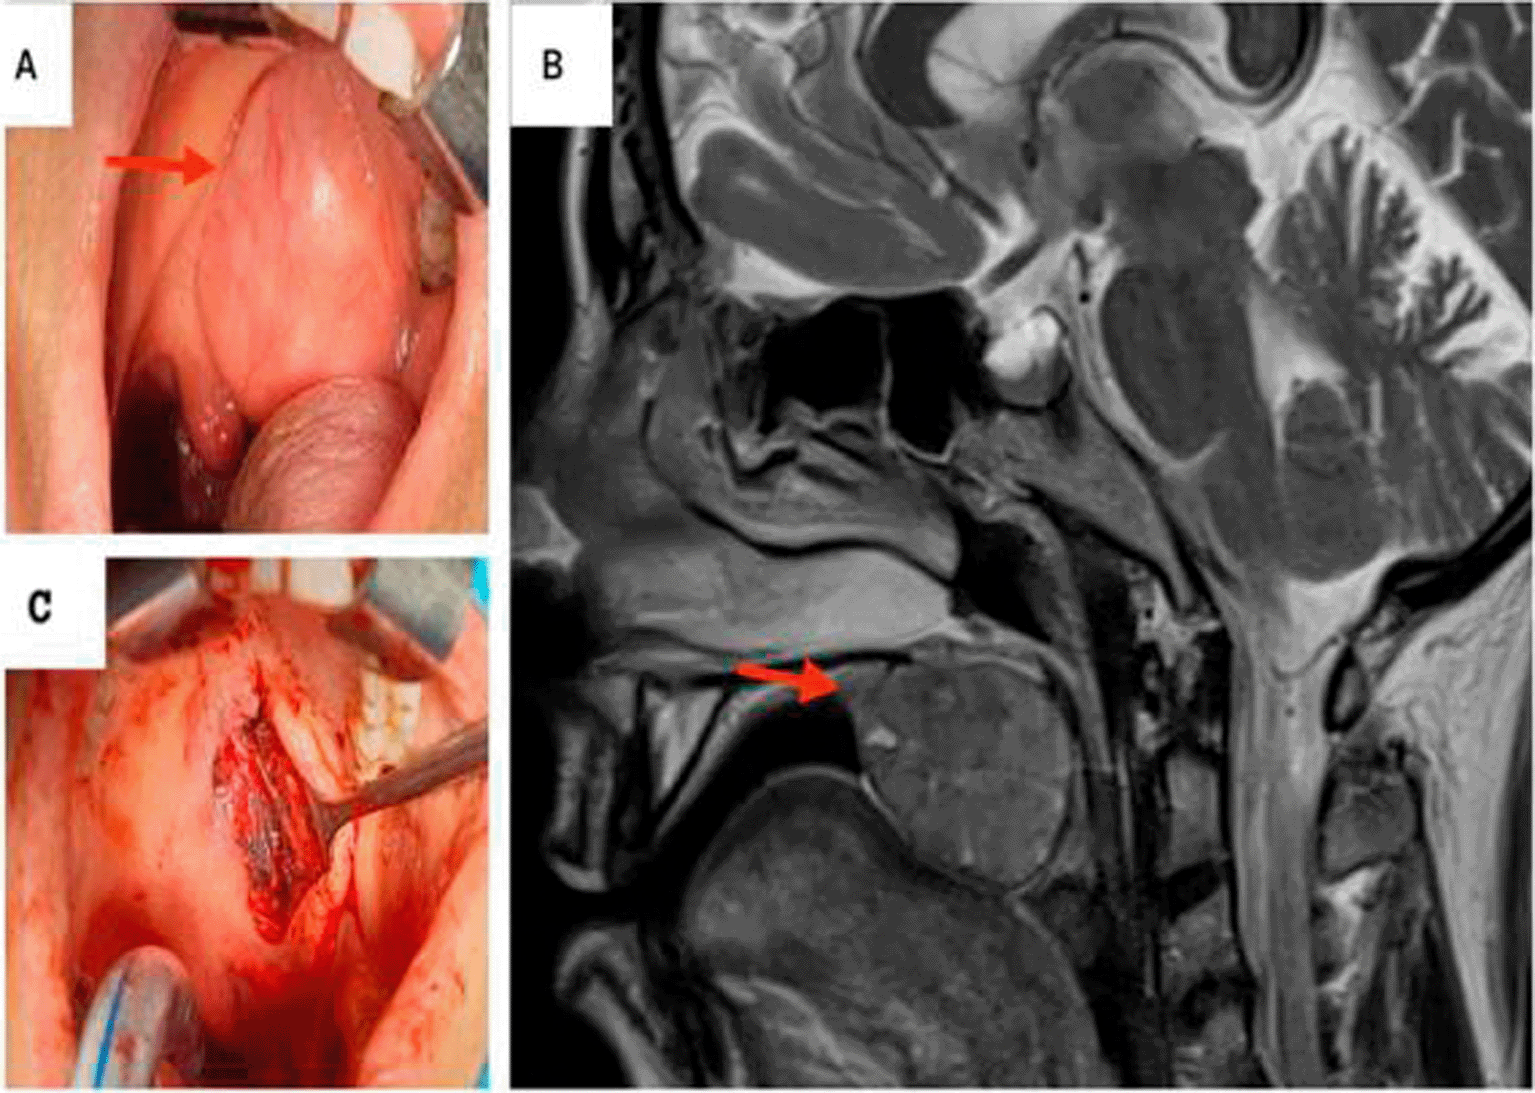

Intraoral examination revealed a unilocular, mobile, fibrous, endophytic nodule at the junction of the soft and hard palates, measuring approximately 4 cm in diameter. The nodule was well delimited, with a regular contour, smooth surface, and normal overlying mucosa color (Figure 2A). No lymph node involvement was observed during the physical examination.

A: Preoperative view: Exposure of the mass in the palate. B: T2-weighted MRI showing a hyposignal ovoid well-defined mass within the right soft palate. C: Peroperative images: the defect post excision of the mass.

Magnetic resonance imaging (MRI) revealed an ovoid well-circumscribed encapsulated mass measuring 3.7 cm in size, within the midline of the soft palate to its right para-median side. The lesion extended backward to the oropharynx and forward in the left tonsillar pillar (Figure 2B).

The mass was completely excised with safety margins via an intraoral approach (Figure 2C).